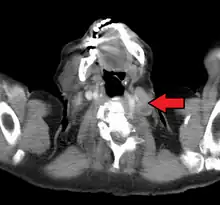

An enlarged Virchow's node as seen on CT